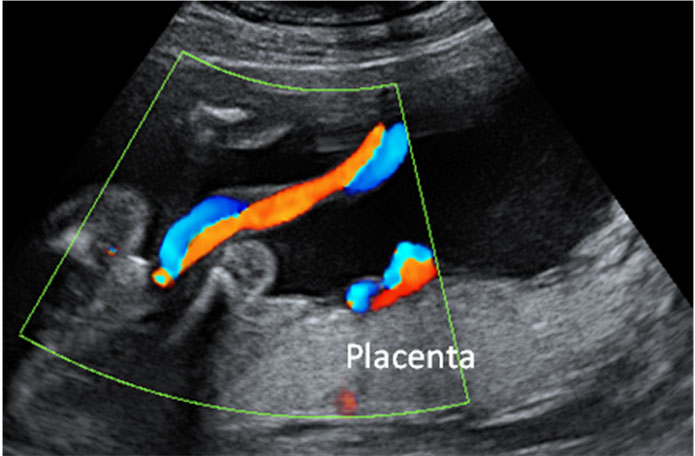

El médico analiza la sangre fetal obtenida por cordocentesis (punción del cordón umbilical a través del abdomen materno). Se estudian los cromosomas sexuales en la sangre. La técnica coincide con la de la amniocentesis, y como esta también se lleva a cabo para detectar alteraciones en el número de cromosomas y malformaciones congénitas, entre otras cosas. Se realiza hacia la semana 19 y no antes. La gestante es sedada suavemente para que esté más relajada y ante posibles dolores. El riesgo de aborto es mayor que en el caso de la prueba de la amniocentesis.

Se estudia una muestra del tejido placentario, lo que se llama biopsia corial . Se trata igualmente de determinar si los cromosomas sexuales son XX (mujer) o XY (hombre). Esta técnica consiste en una punción que puede hacerse por vía vaginal o por vía abdominal y se realiza a partir de la semana 11. El riesgo de aborto es mayor que en una amniocentesis. Su ventaja sobre ella es que los resultados se obtienen en menos tiempo.